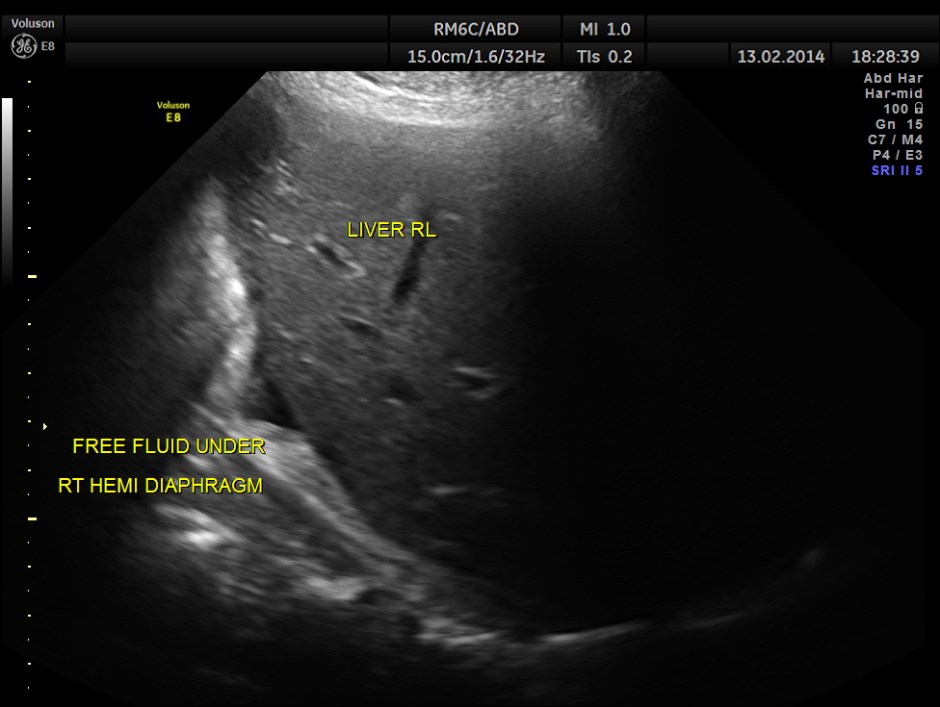

This was a 61 year old gentleman , who presented with complaints of acute abdominal distension , pain and history of constipation of 3 days duration . He showed the following findings :

minimal free fluid in the abdomen